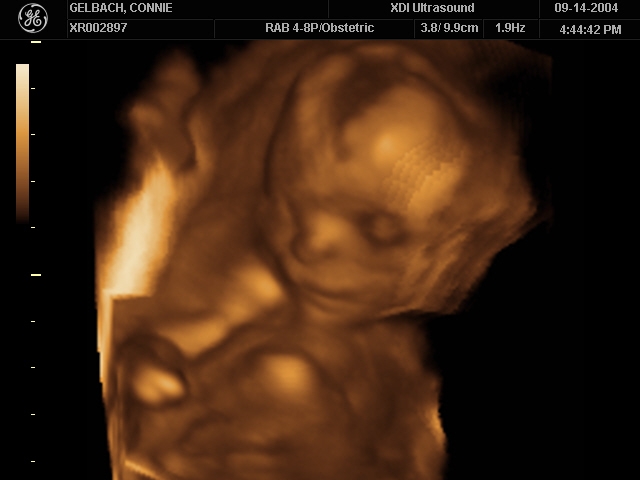

Sonograms